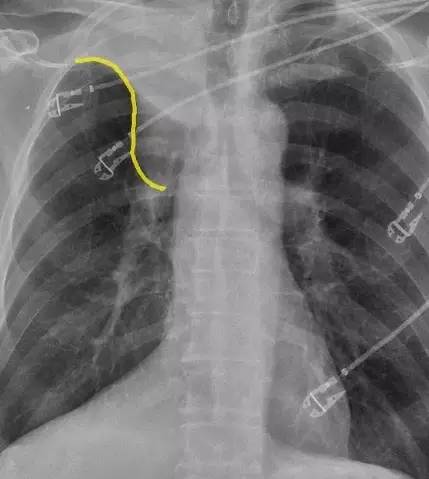

图 1. 正位胸片示「反 S」征(黄线示)

「反 S」征指的是右肺上叶膨胀不全,水平裂向上移位,右肺门肿块共同形成胸片上反 S 形的凸出影。现结合 Zachary Laste 博士近日在 ACR 上发布的一例右上肺癌的病例对「反 S」征进行介绍。

「反 S」征指的是右肺上叶膨胀不全,水平裂向上移位,右肺门肿块共同形成胸片上反 S 形的凸出影。肺癌是引起「反 S」征最常见的病因。其他病因有转移淋巴瘤、压迫气道的纵膈肿瘤以及支气管内的转移灶。一旦胸片上发现「反 S」征,就需要 CT 检查来评价病灶的恶性程度。

「反 S」征是正位胸片上一个经典的影像学征象,最早由 Ross Golden 医生描述。S 征是由右肺上叶不张,水平裂向上中移位,中央型肿块向右肺门突出共同形成。正位胸片的典型表现包括水平裂向上凹陷,并向上内侧移位,以及肺门肿块形成的凸起。侧位胸片上,肺大间裂向前上移位是典型的表现。